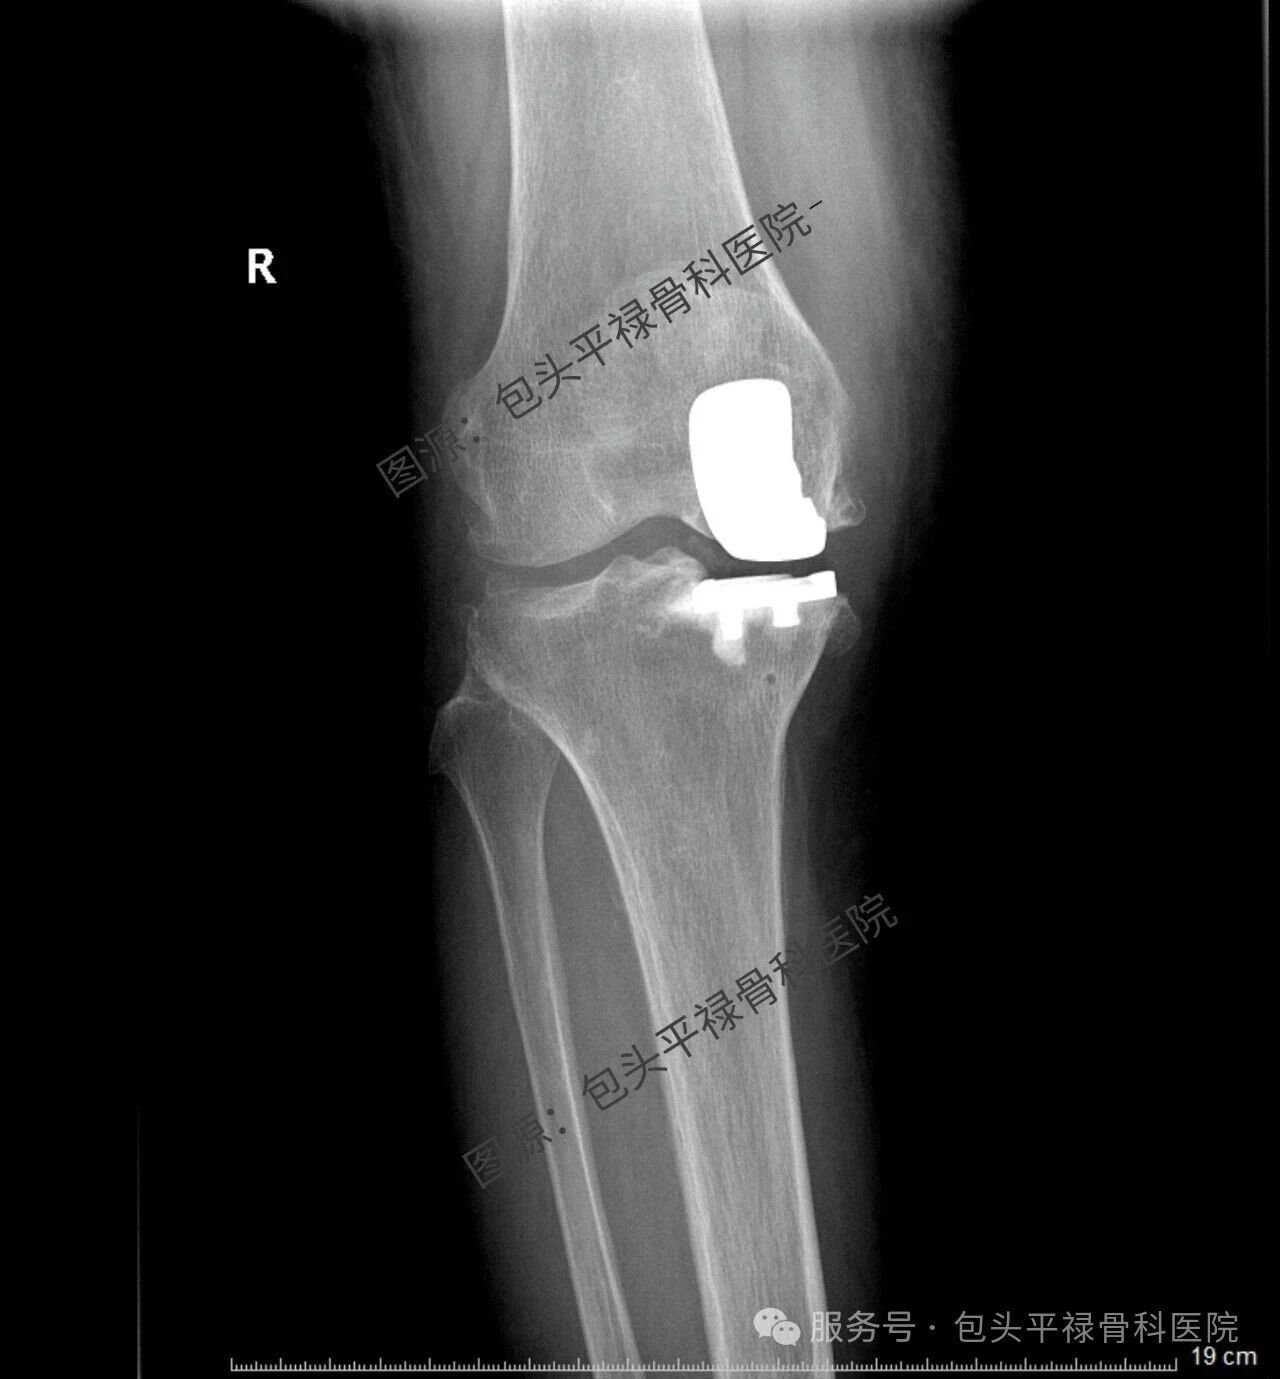

其实,现代医疗技术日趋精准,如果患者的关节炎只局限于膝关节的一个部分(单侧间室),那么TA很可能适合一种更为精准、创伤更小的手术——膝关节单髁置换术。

膝关节单髁置换术相当于“局部翻新”,就是只置换“坏掉房间”的磨损表面,仅将受损的软骨和部分骨质去除,替换为人工假体,而完好的软骨、交叉韧带及其他结构都得以最大程度的保留。

单髁置换术的突出特点是什么?

创伤更小:手术切口短,对软组织损伤小。

出血更少:术中出血量少。

恢复更快:术后当天或次日即可下地,住院时间短,康复速度更快。

感觉更自然:保留了膝关节大部分正常结构和韧带,术后本体感觉更好,上下楼梯、下蹲体验佳。

功能保留更多:术后膝关节活动范围通常更大。